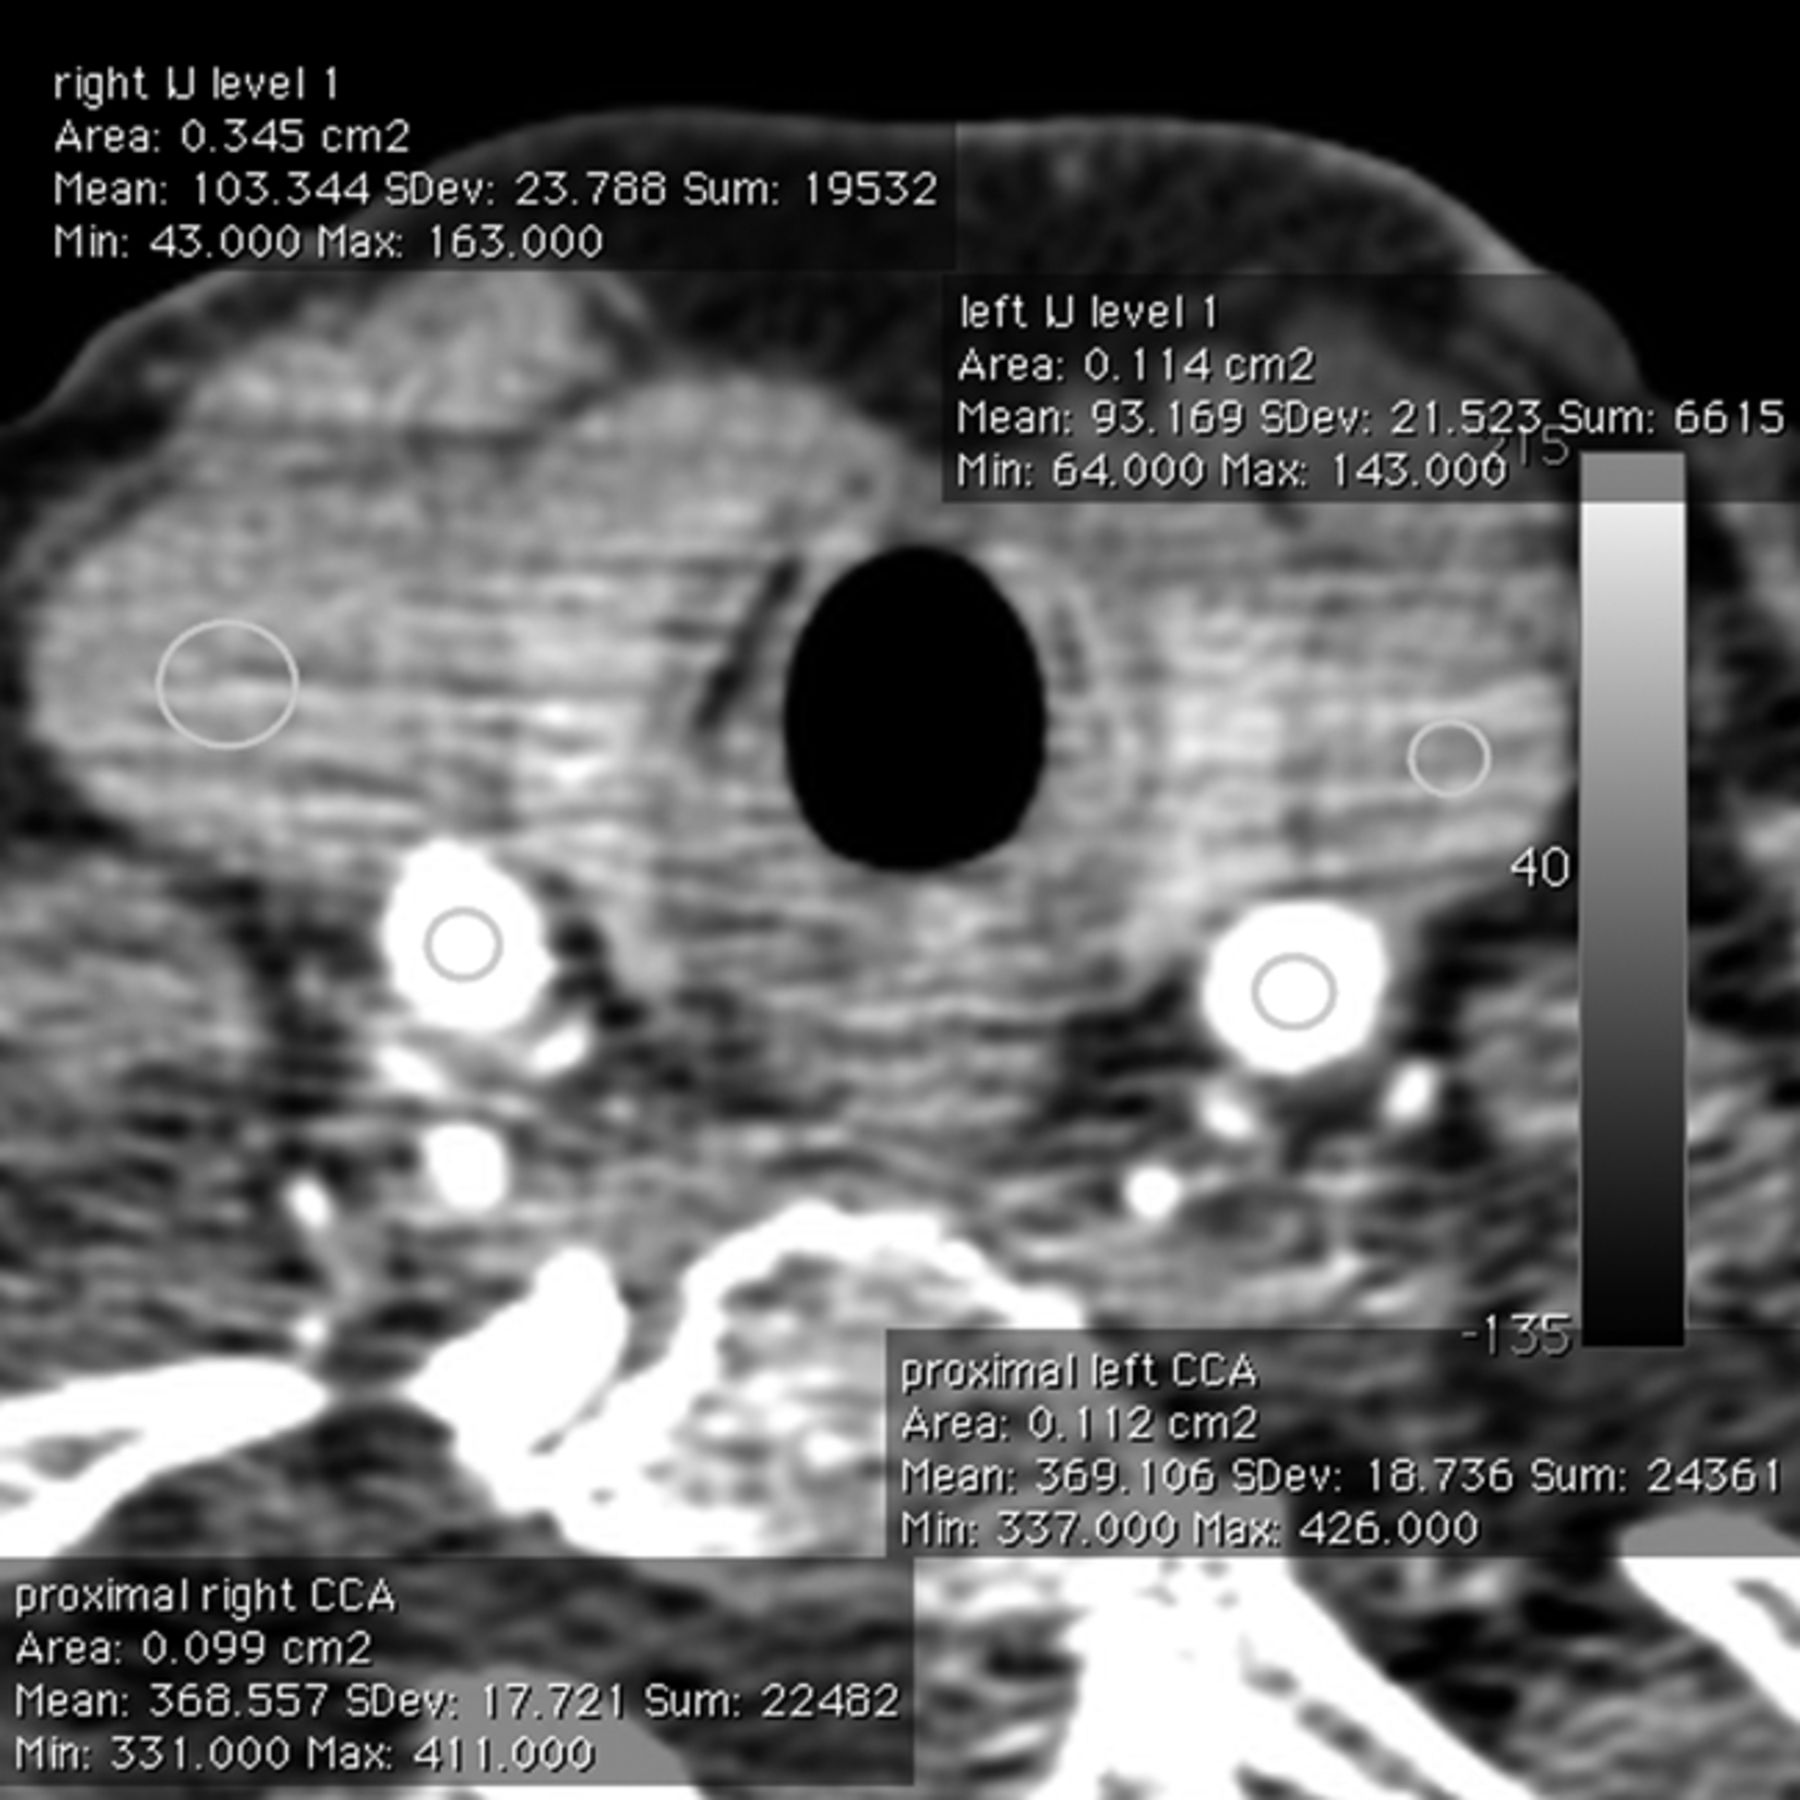

Quantitative evaluation was performed on a separate workstation (MacPro, Apple, Cupertino, California) with the use of the OsiriX DICOM viewer (OsiriX Imaging Software; http://www.osirix-viewer.com), with placement a circular region of interest within each vessel at the 9 levels of interest; measurements were made in the aorta and the 4 levels of each carotid described above (Fig 2). The mean attenuation and standard deviation were measured for each artery by placement of a circular region of interest within the contrast-enhanced lumen of each segment. The regions of interest were sized to fill most of the intravascular space without including the vessel wall. Regions of interest typically measured approximately 10 mm2. Areas of vascular calcification were avoided. Adequate arterial opacification is regarded as >150 HU. Adequate arterial-venous segment contrast is regarded as >50 HU.

Axial image from a 256-detector CT angiogram at the level of the proximal CCA and proximal IJVs. Regions of interest show excellent arterial opacification (right CCA, 368 HU; left CCA, 369 HU) and sufficient contrast with the adjacent venous segment (right IJV, 103 HU; left IJV, 93 HU). Mild venous enhancement is typical, given that CTP is performed before CT angiography.

Attenuation values of the veins at 9 corresponding locations were also noted: measurements were made in the superior vena cava and IJV on each side adjacent to the arterial measurement. To obtain the attenuation value, a circular region of interest (of the greatest diameter that would fit in the vessel lumen) was drawn on axial images in the center of the lumen. The typical size for such regions of interest was 15 mm2. The mean and SD values were recorded for each site. Both experienced CTA reviewers recorded artifacts during their evaluation of the carotid vasculature. Evaluation focused on artifacts that caused obscuration of arteries and limited diagnostic evaluation of that region. Artifacts were assigned to 1 of the 7 following categories: